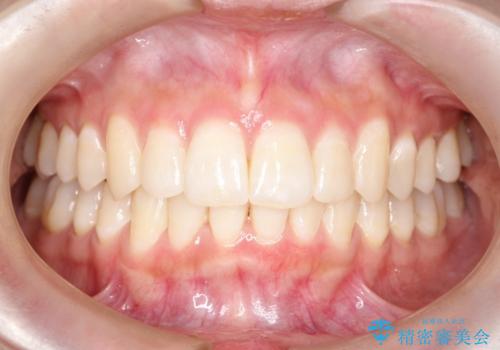

20代女性 わずかな歯並びの修正(invisalignにて)

- 7ヶ月

- 10-30回

・切端咬合気味であった前歯の咬み合わせの関係

・前から2番目の歯がねじれており、部分的な反対咬合となっている

の改善を行いました。

写真ではわかりづらいですが、患者さんの希望により上下の歯をより内側に引くような動きを併行させています。